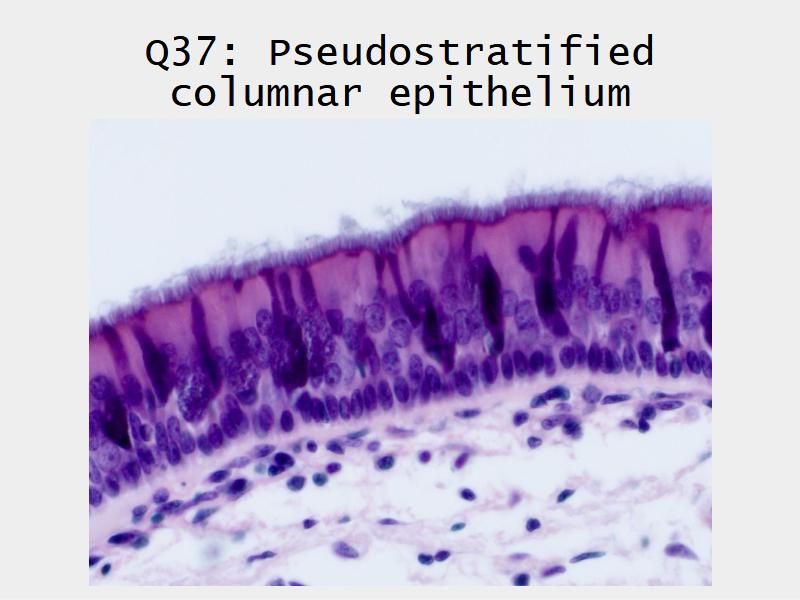

Respiratory epithelium

- Pseudostratified

- Ciliated

- Columnar

- Epithelium with

- 4 Cells

- Ciliated columnar cells

- Non-ciliated columnar cells

- Goblet cells

- Basal cells